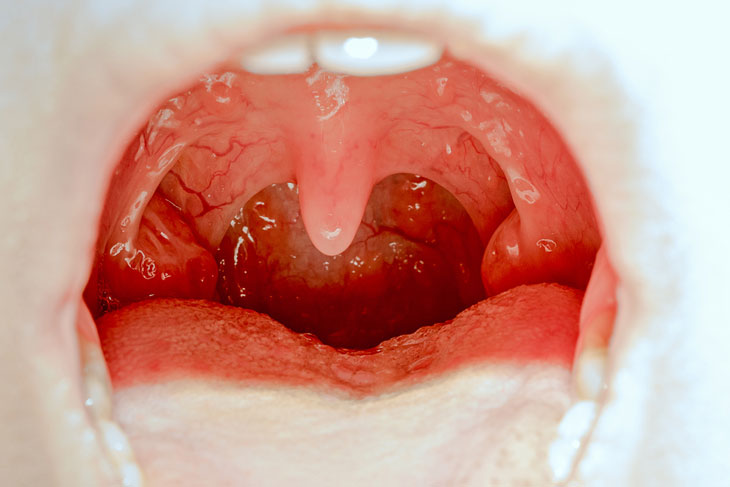

4. Viêm amidan

+ Amidan là tổ chức đóng vai trò quan trọng giúp cho cơ thể sinh ra kháng thể để chống lại các vi khuẩn, virus gây bệnh. Tổ chức này cũng có thể bị viêm khi có nhiều vi khuẩn, virus xâm nhập điều đó khiến cho amidan quá tải gây ra viêm.

+ ở giai đoạn cấp tính khi amidan mới khởi phát có thể gây ra các triệu chứng sau: sốt, đau họng, chảy nước mũi, hai amidan sưng cứng,….. các biểu hiện này thường gây ra cảm giác đau nhói vùng họng, khan tiếng, hơi thở hôi, thỉnh thảng kho han,….

+ sang giai đoạn mãn tính, khi các triệu chứng đã chuyển sang nặng hơn. ở giai đoạn này, viêm amidan sẽ tái đi tái lại nhiều lần , amidan sưng to khi ăn, gây khó thở, và sẽ dẫn đến các biến chứng nguy hiểm khác thì người bệnh cần phải phẫu thuật để loại bỏ amidan.